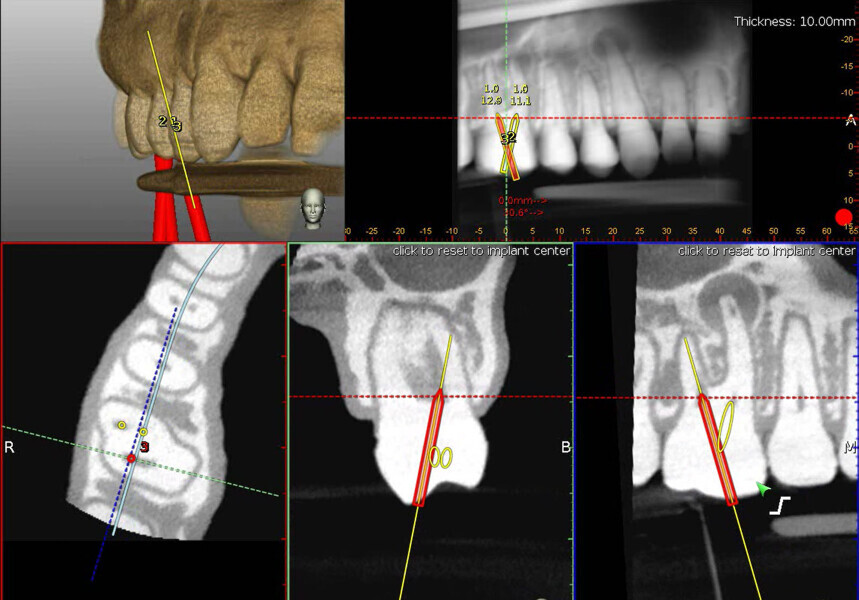

Fig. 9a: Calcified central incisor: (1) the drill is green; (2) the central axis of the glide path or osteotomy; (3) the depth indicator; (4) the angle between the drill and central axis of the planned osteotomy. When the drill and the central axis overlap, the depth indicator turns yellow. (Courtesy of Dr Bobby Nadeau)

Fig. 9b: Maxillary molar: the planned canal location is on target (yellow: 0 mm). (Courtesy of Dr Bobby Nadeau)